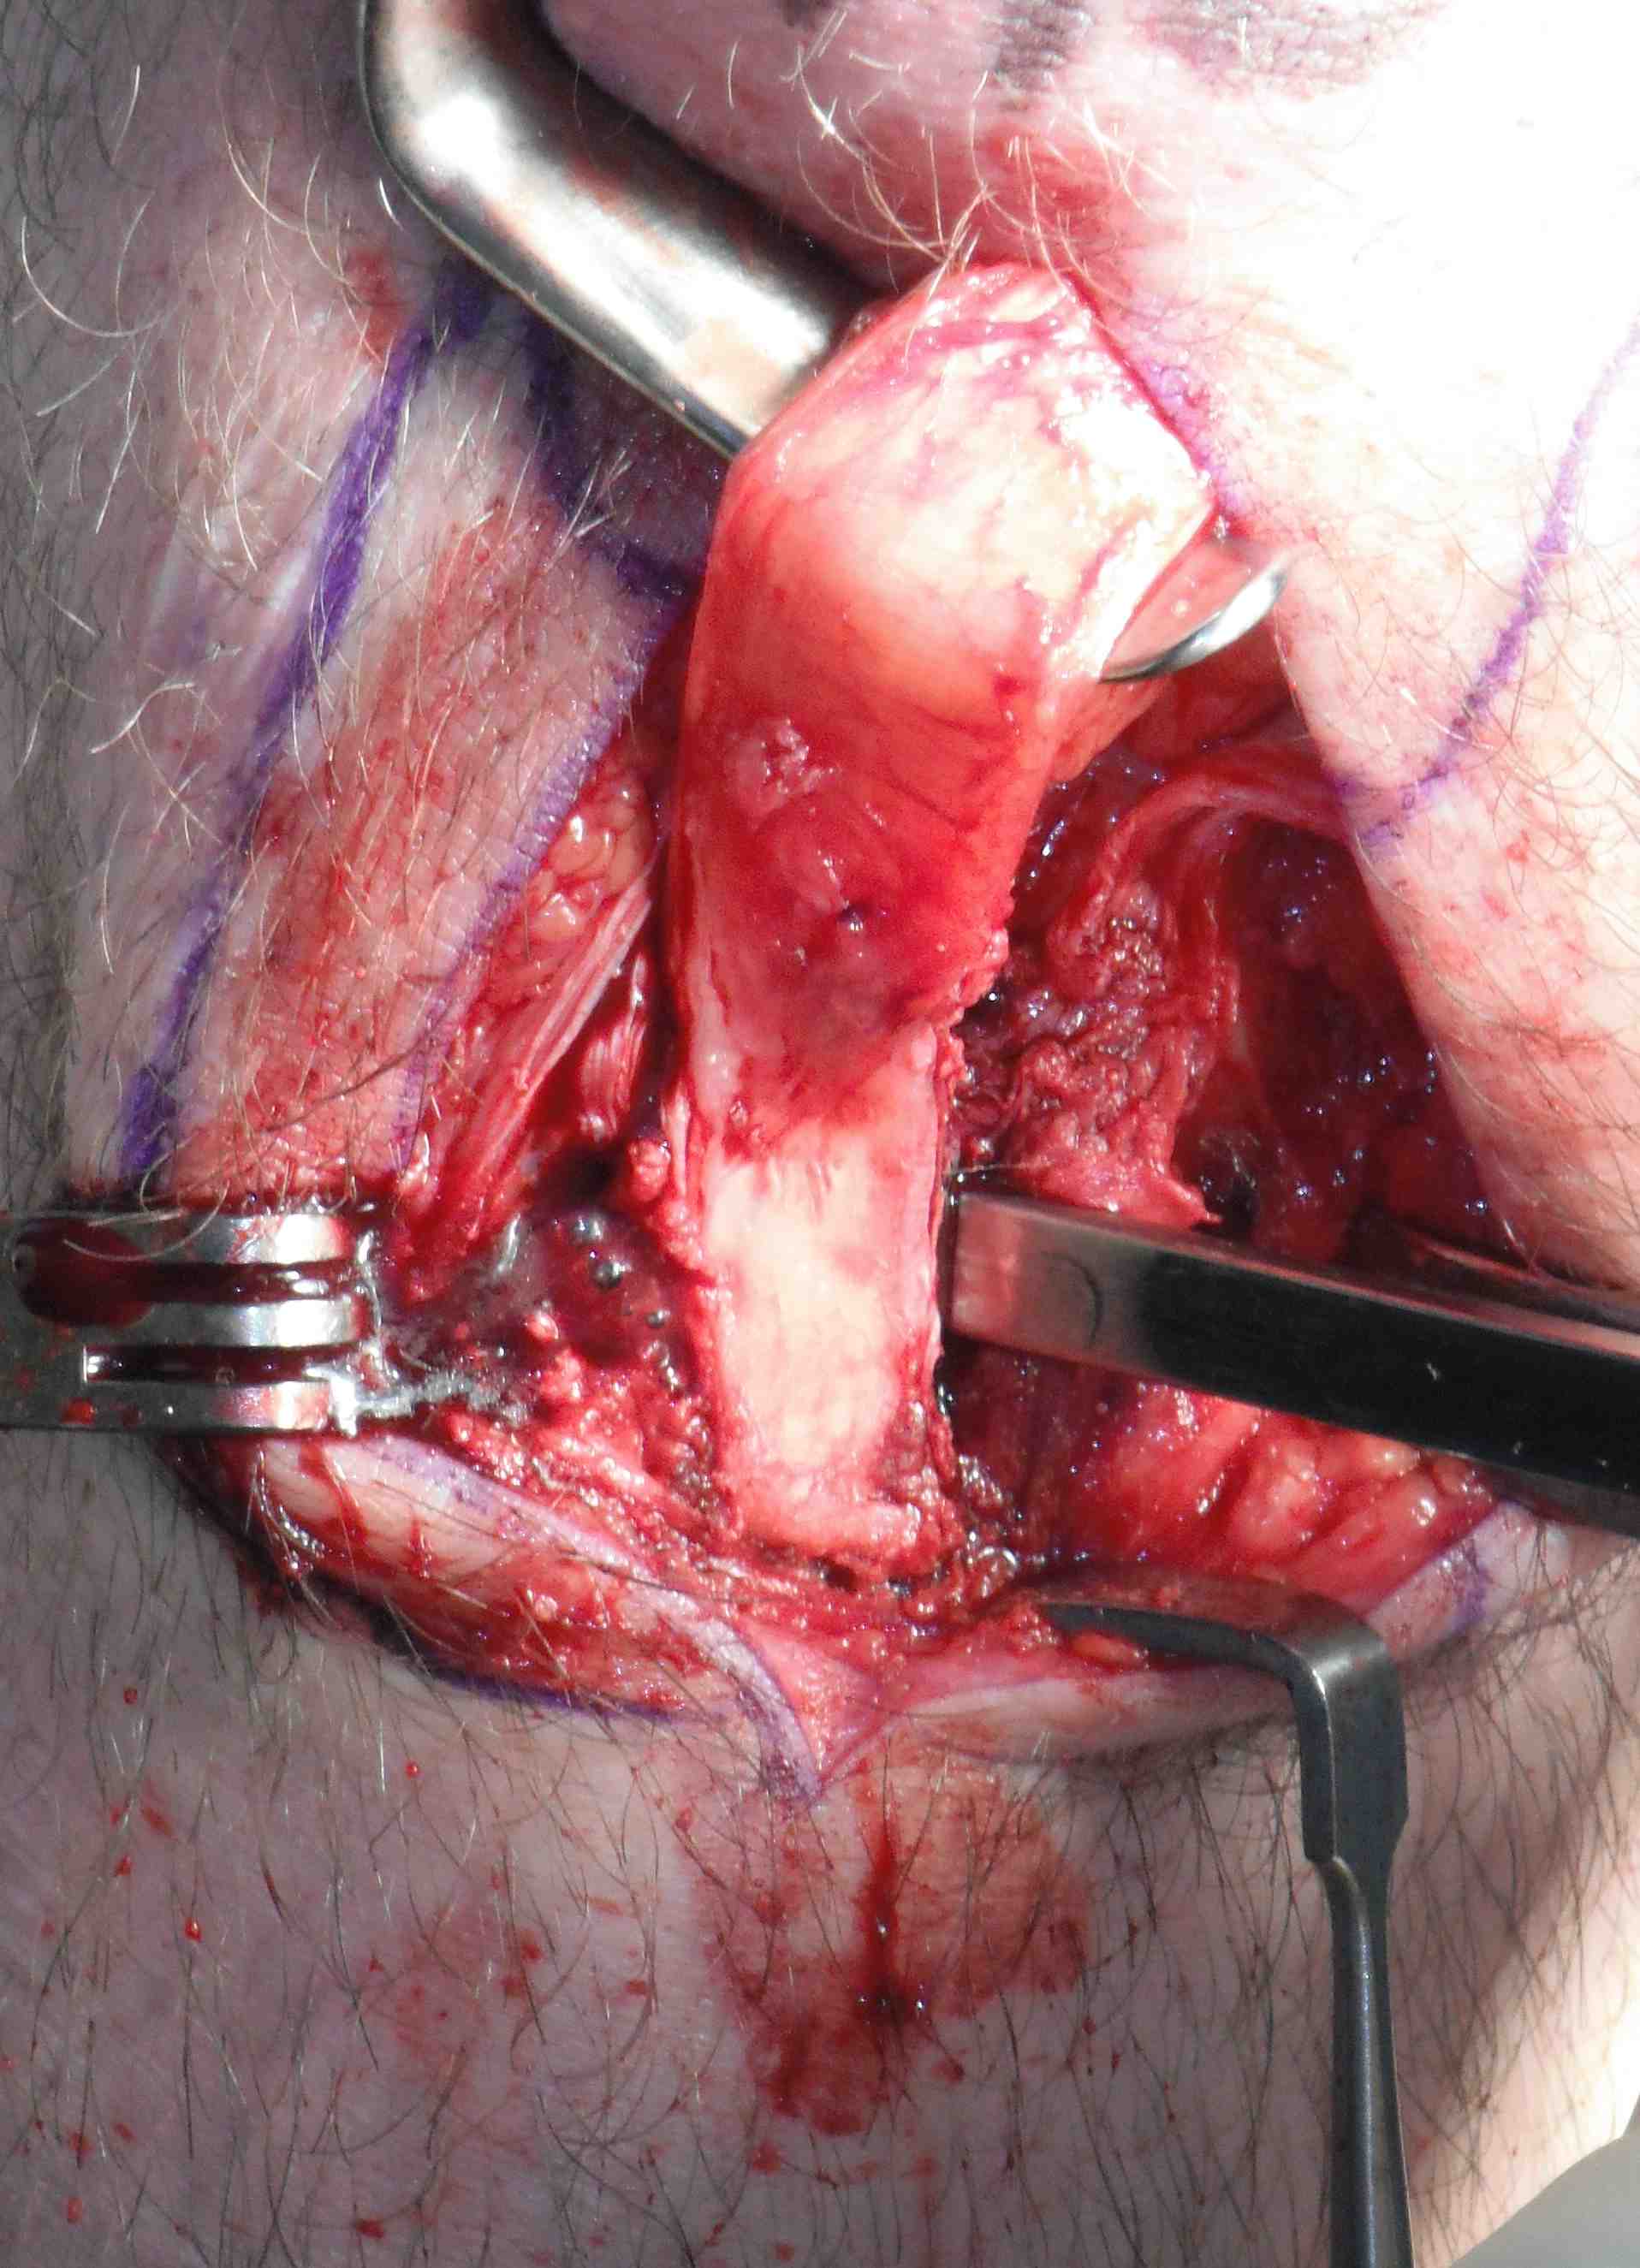

Graft preparation

Clean tendon of soft tissue

- decide which end will pass into femur

- usually the smaller piece

- nibble any sharp edges off especially on leading edge

- ensure whole graft will pass through 10 mm tube

- decide which end will be tibial or femoral

- mark femoral end with blue pen

- put 2 x 1 non absorbable sutures through drill holes

- probably don't need to tension BPTB